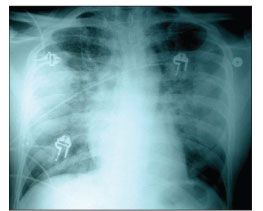

Figure 1. Chest radiograph demonstrating bilateral interstitial infiltrates.

A chest radiograph showed bilateral interstitial infiltrates (Figure 1). Because there was a concern for P jiroveci pneumonia (PCP), the patient was empirically treated with high-dose trimethoprim/sulfamethoxazole and corticosteroids. Azithromycin and ceftriaxone were also administered to cover potential community-acquired pneumonia pathogens.